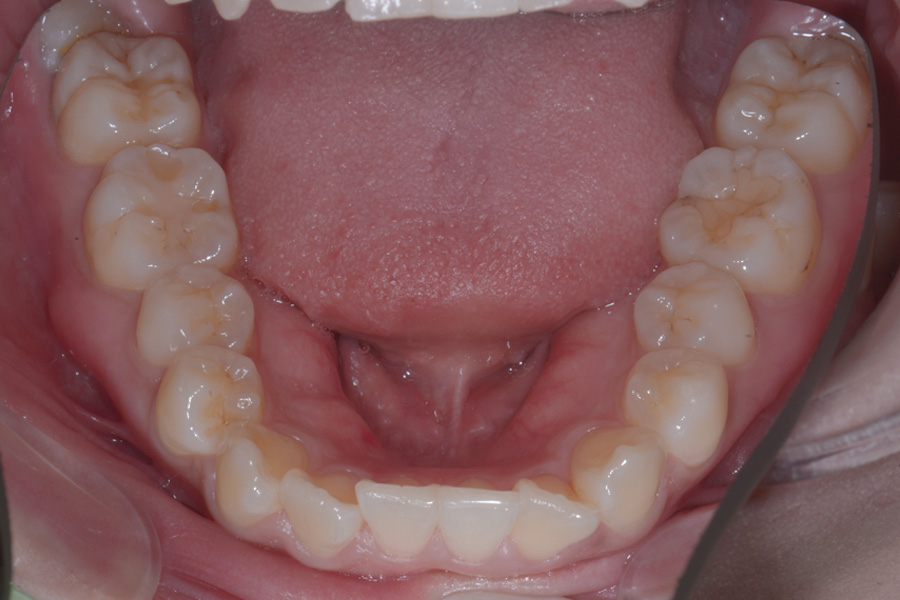

【20代女性】

飛び出ている2本の歯を引っ込めて

下の捻じれている歯を並べたい

治療後

主訴 飛び出ている2本の歯を引っ込めて下の捻じれている歯を並べたい

治療内容 ハーフリンガル矯正(上顎裏側・下顎表側矯正)